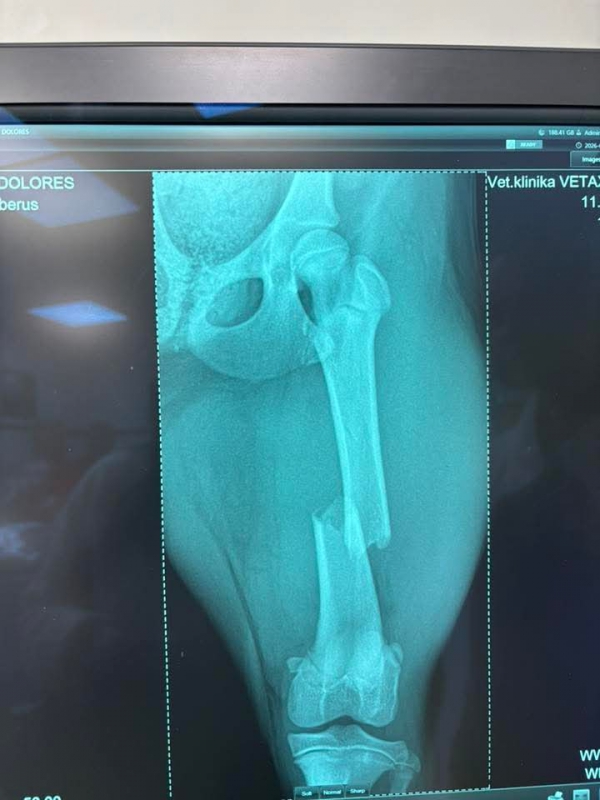

Včera sme prijali toto zranené šteniatko. Fenka zostala na pozorovanie na veterine a zistili že má zlomenú stehennú kosť :(

DOLORES má po operácii ♥. Ďakujeme všetkým za pomoc ♥♥♥. Držte malej palce aby bola čoskoro fit :)

Dolores po operácii pozdravuje. Zotavuje sa výborne a rýchlejšie ako sme mysleli ♥♥♥